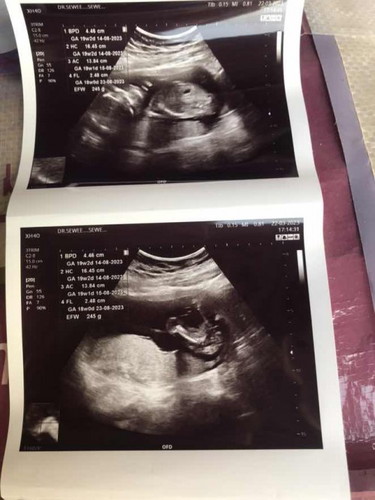

ดูตรงไหนคะถึงเป็นเพศชายคะ

ตรงระหว่างขาค่ะ รูปล่างค่ะ อันนี้ของเรา ช เหมือนกันค่ะ